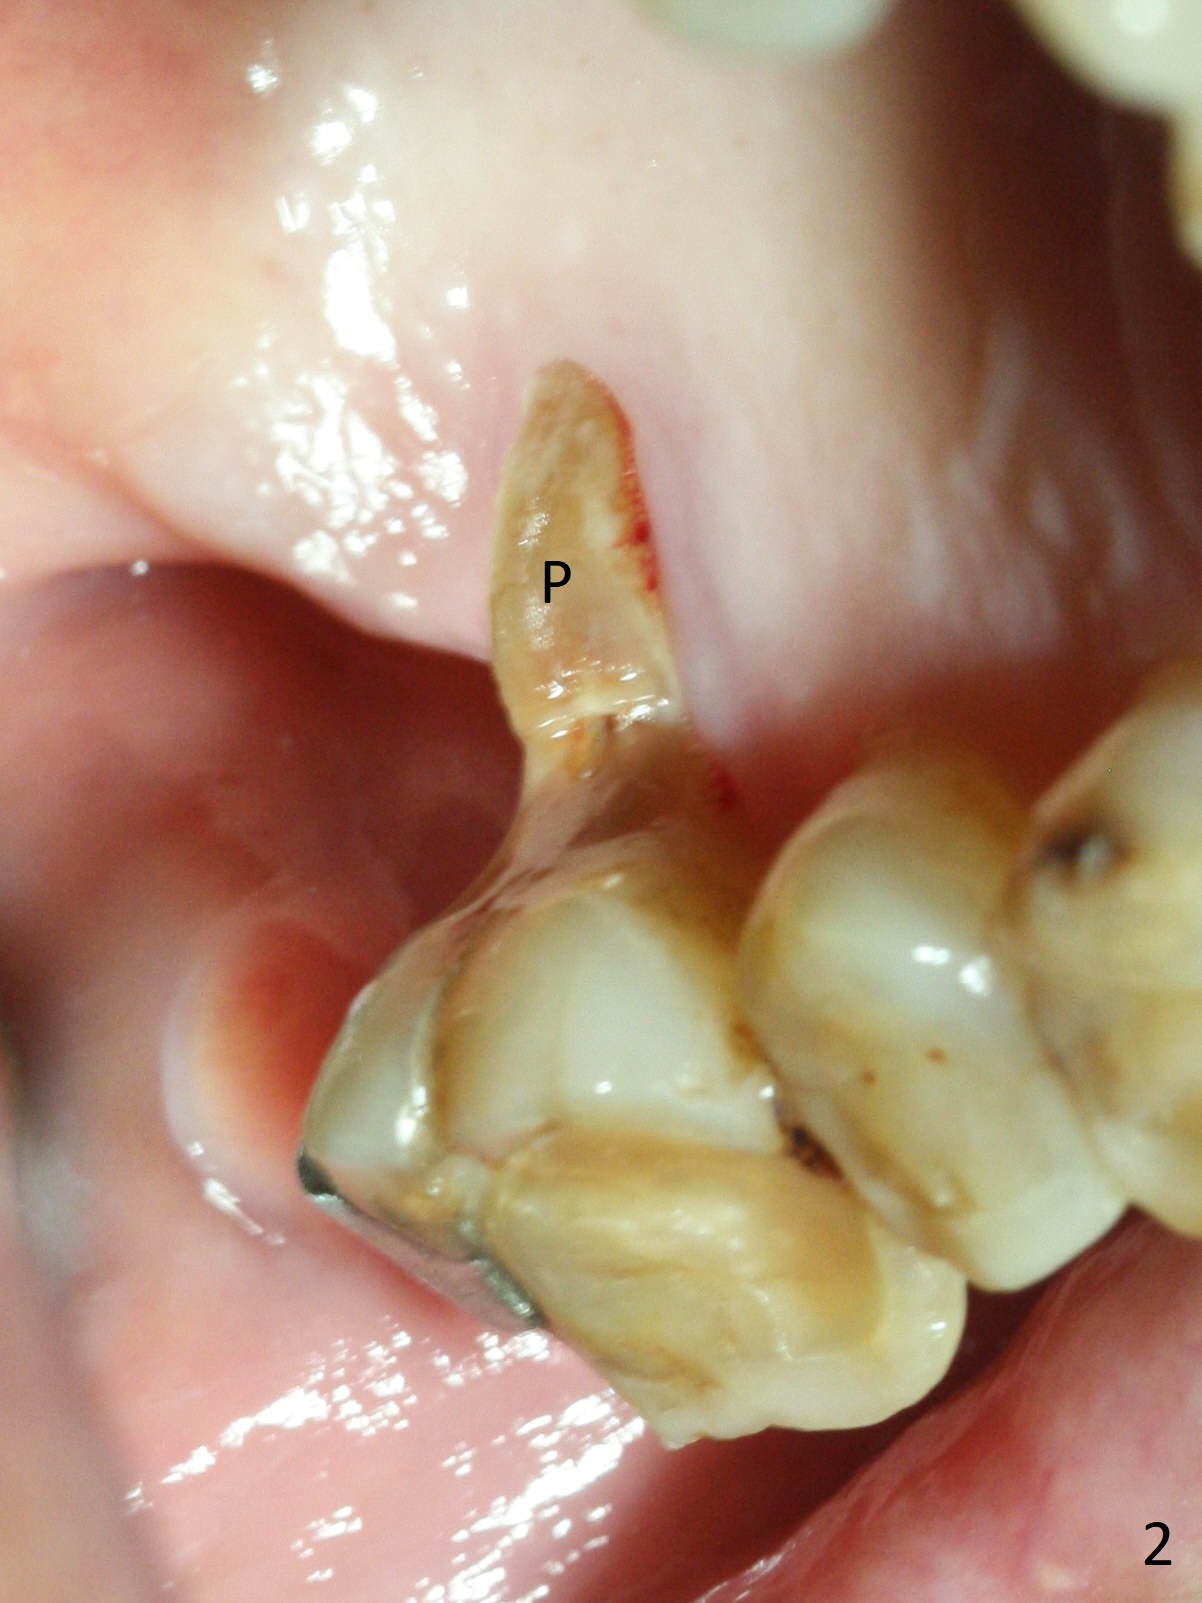

A 88-year-old man cannot masticate well on the left side because of the loose tooth at #14 with severe gingival recession buccal (Fig.1) and palatal (Fig.2 P). An implant will be placed in the septum; the peripheral defects of the sockets will be covered by PRF (x2) before bone graft. Initial depth of osteotomy will be 11 mm (Fig.3) with the implant length being 13 mm. Because of severe vertical bone loss, a mill abutment is expected (Fig.4). In fact CT shows the buccopalatal bone is wide. Use IS implant if it arrives. But cementation abutments are not available. A temporary abutment may be used. The patient is nervous about PRF.